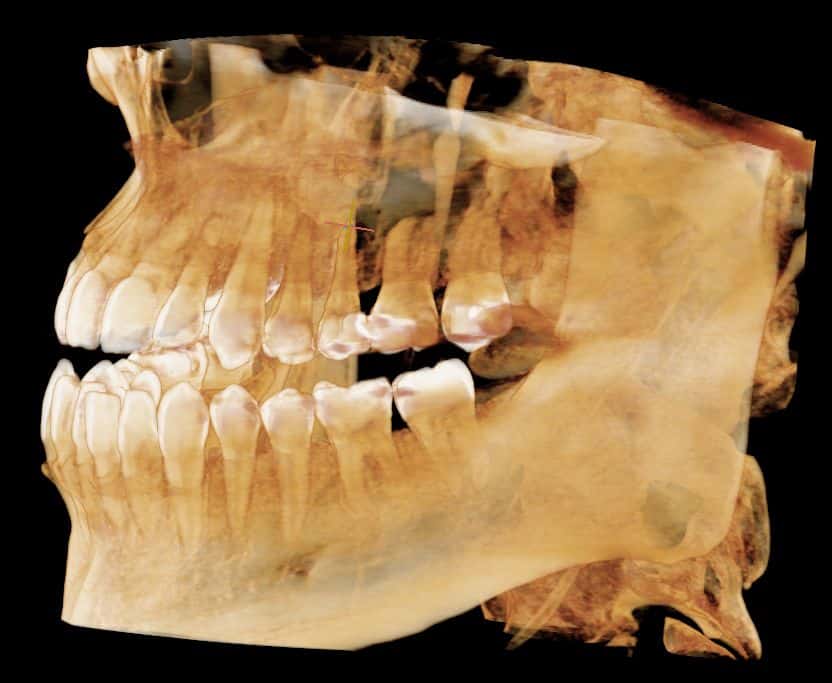

Dr. Lee is truly the best dentist I've ever seen. He placed my implant, and I couldn't be happier. His genuine care for my comfort and safety made all the difference. So glad I finally switched to this practice!